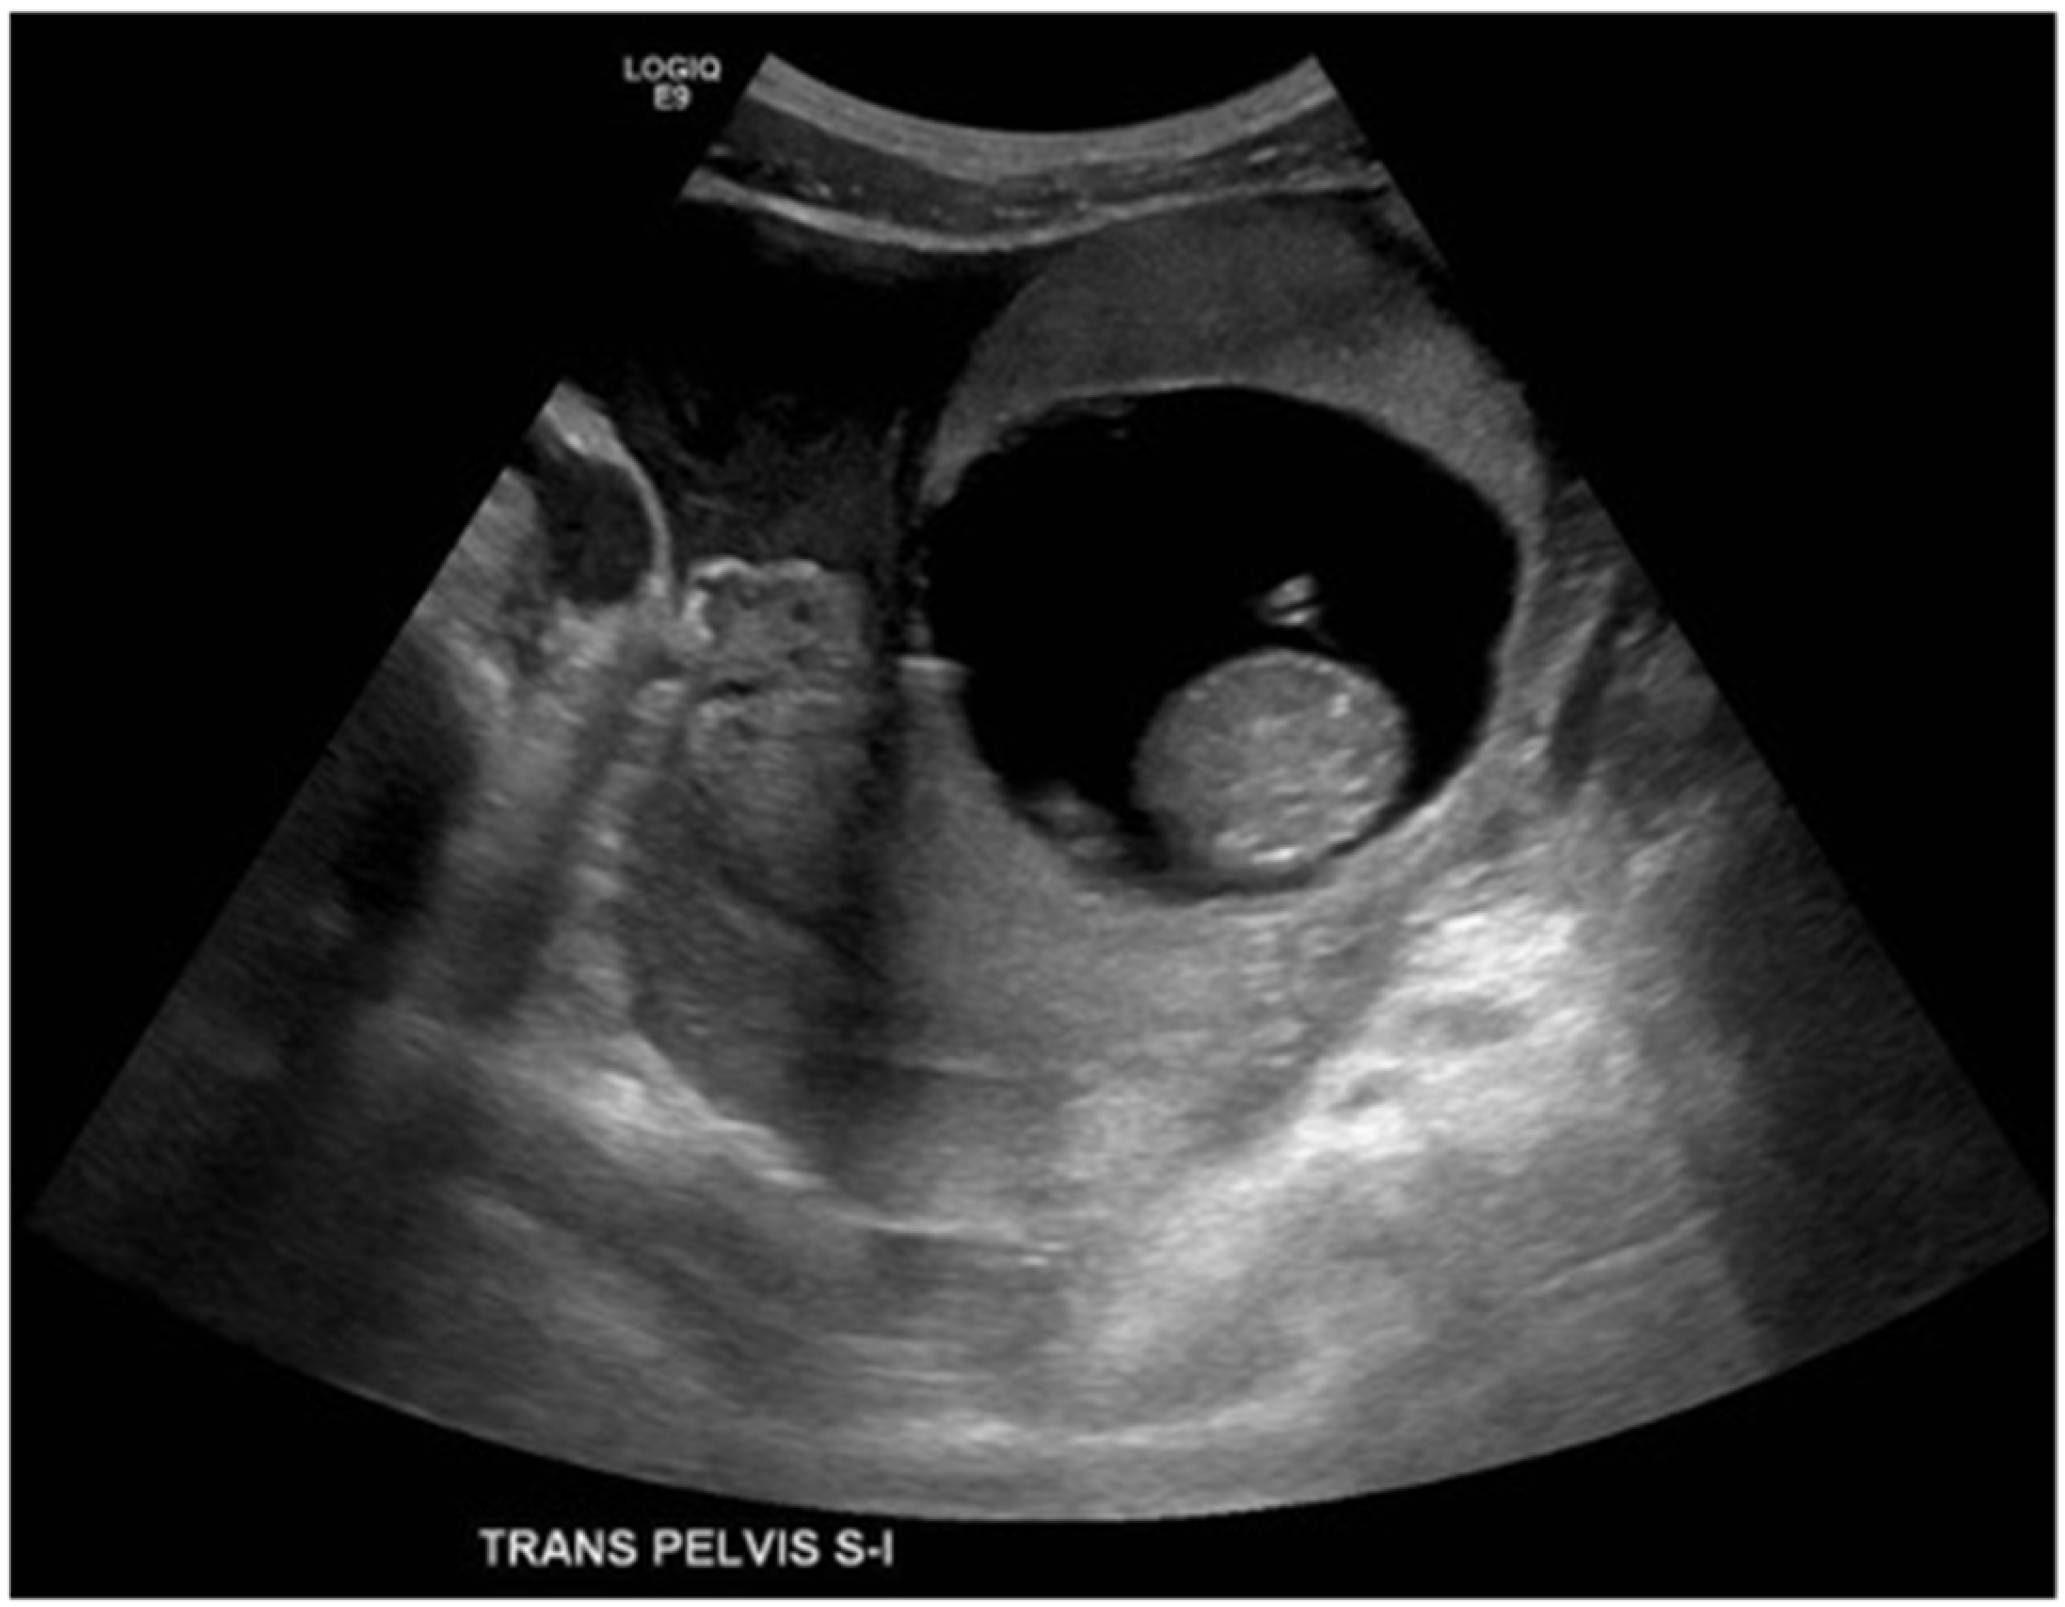

Figure 2.

MRI without contrast showed that the ectopic gestational sac exerted mass effect upon the uterus and bladder, and was associated with a moderate amount of pelvic fluid. (a) Axial T2 HASTE demonstrating ectopic pregnancy in the left adnexa with associated mass effect on the bladder and uterus which deviate to the right. The placenta is located anteriorly within the gestational sac. (b) Sagittal T2 HASTE demonstrating ectopic pregnancy located anterior to uterine fundus and superior to bladder. The anterior wall of the gestational sac is located approximately 1.3 cm deep to the overlying skin surface. There is a moderate amount of complex free pelvic fluid. (c) Coronal T2 HASTE demonstrating intact gestational sac superior to the bladder in the left adnexa. The left ovary is partially visualized superior to the gestational sac and contains an incidental 2.0 cm follicle.